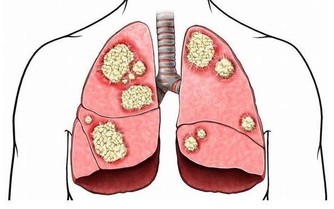

5、別等病了再體檢,防大病

許多人對自身健康不重視,出現頭暈、胸悶、心悸、胃痛、失眠、食慾差等症狀也不在乎,但武漢大學中南醫院心內科博士陳明提醒,這些都可能是疾病的信號,比如胸悶、心悸可能與心髒病有關,頭暈或許是高血壓的前兆等。許多癌症早期治療會比晚期治療存活率高許多,比如早期胃癌及時治療5年生存率可達60%~90%,而晚期胃癌5年生存率僅有6%~30%。所以,最好每年定期到醫院做一次體檢,查查血糖、血壓、骨密度等項目,男性要查前列腺,女性要查乳腺,以免小病等成大病,失去治療良機。